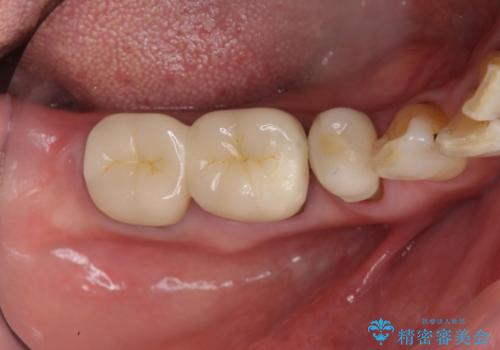

- 他院で右下小臼歯が保存不可能と言われ来院。当院の判断でも残念ながら抜歯となり、欠損部は抜歯後ブリッジにしました。右下奥2本が連結されていたため、そこは各々切り離した形で被せ物のやり替えも行っています。

- 約60万円 右下④5⑥:ジルコニアクラウンブリッジ 11万円×3 仮歯 1万円×3 根管治療費用別途費用は治療当時の料金となります

抜歯後3か月ほど仮歯で生活していただき、欠損部の歯肉の状態が安定してからブリッジを入れています。